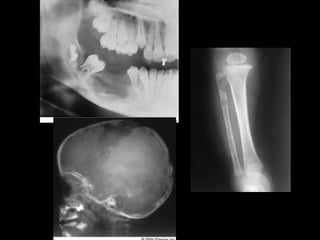

2. CT scan in case of larger lesions and esp maxillary

ameloblastoma

1. For the mandible, segmental defects of 5 cm can

be reconstructed with bone grafts most commonly

iliac crest.

2. For more larger defects free osseofasiocutaneous

flaps may be used.. DCIA and free fibular flap.